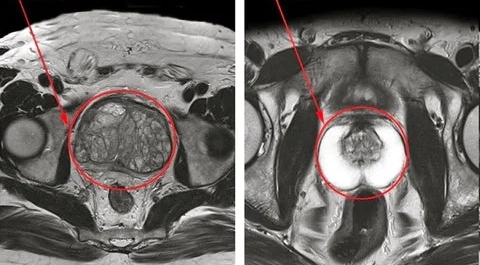

Posteriormente, em seu segundo estágio de ação, ele atua na normalização do tamanho da próstata e na eliminando a hiperplasia prostática benigna (HPB) e a prostatite.